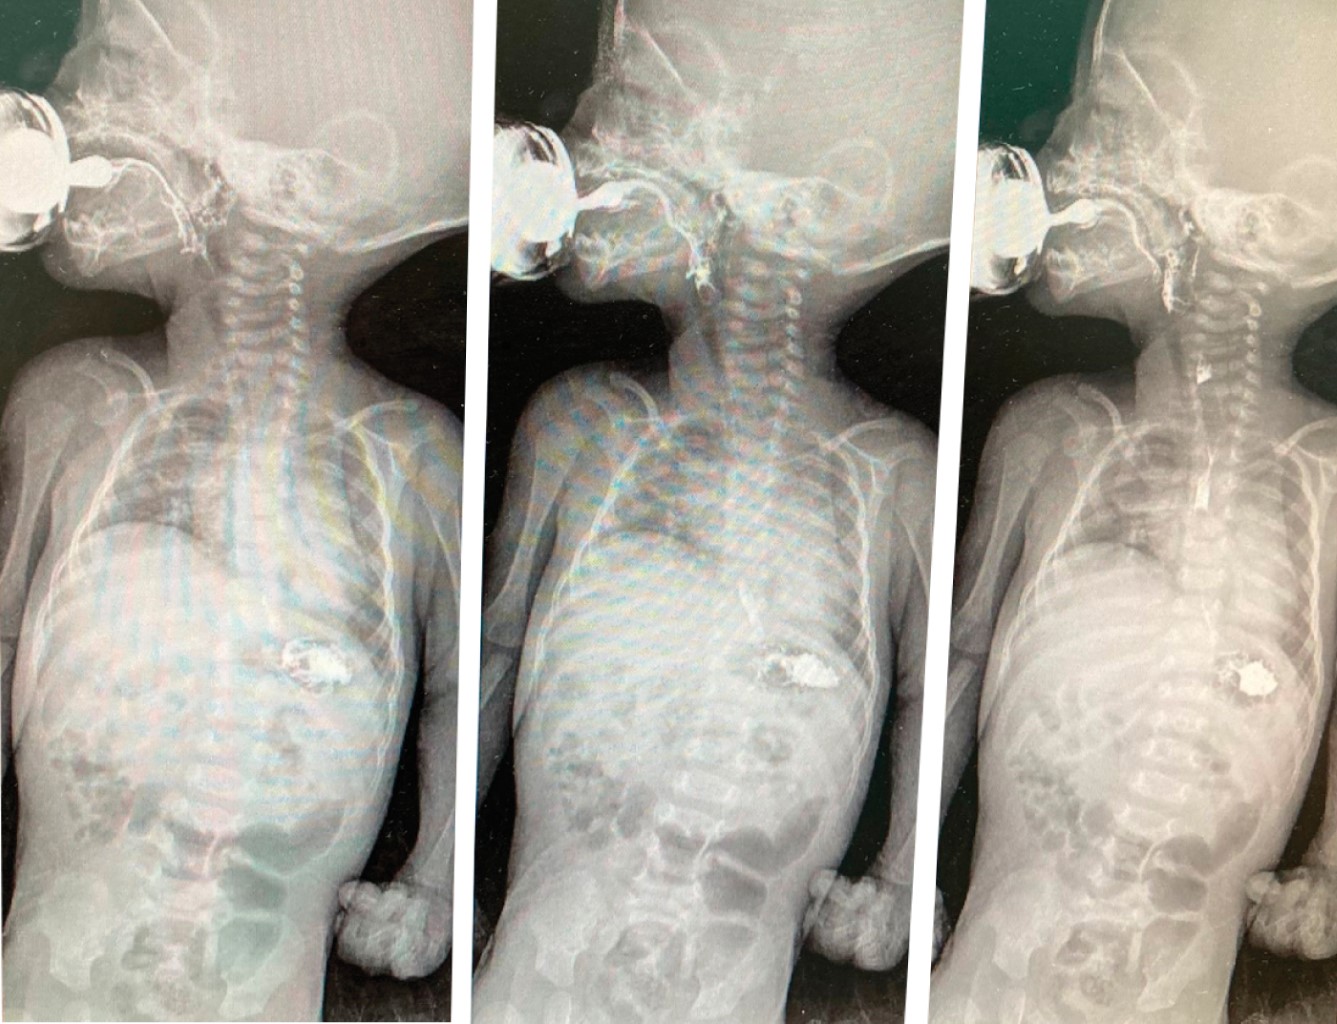

Con la sospecha clínica mencionada se realizó una tomografía simple de tórax que corroboró el hallazgo de la radiografía (Figura 2), así como también una radiografía de tórax anteroposterior en inspiración y espiración bajo seguimiento con fluoroscopia (Figura 3), de esta manera fue diagnosticada con eventración diafragmática congénita que requirió tratamiento quirúrgico. Se llevó a cabo una toracotomía lateral derecha con los siguientes hallazgos: diafragma adelgazado con disminución de la movilidad, rechazado hacia el tórax por el hígado a nivel del cuarto y quinto espacios intercostales. Después de la plicatura diafragmática se colocó sonda pleural durante 72 horas, con mejoría de la función pulmonar (Figura 4).

Figura 2

Figura 3

Figura 4